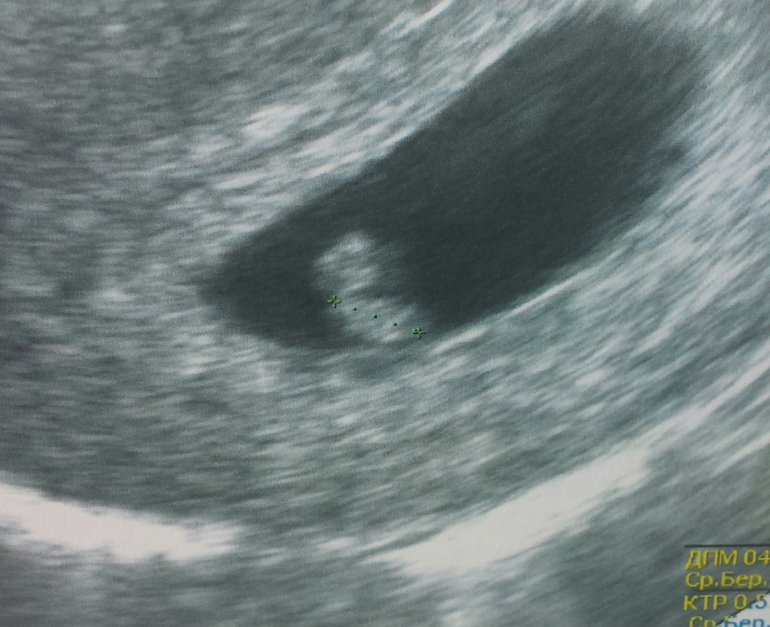

Узи 29 дпп.

Головастик наш живой, сердечко бьется... все соответствует сроку. 6 недель и 2 дня. Сердцебиение 135 я так понимаю хорошее? Вышла от врача , села в машину и реву. ... гребаный эстрадиол! Нафиг сдавать если сделать ничего не сможешь, а только мозг взорвешь себе! И всем!